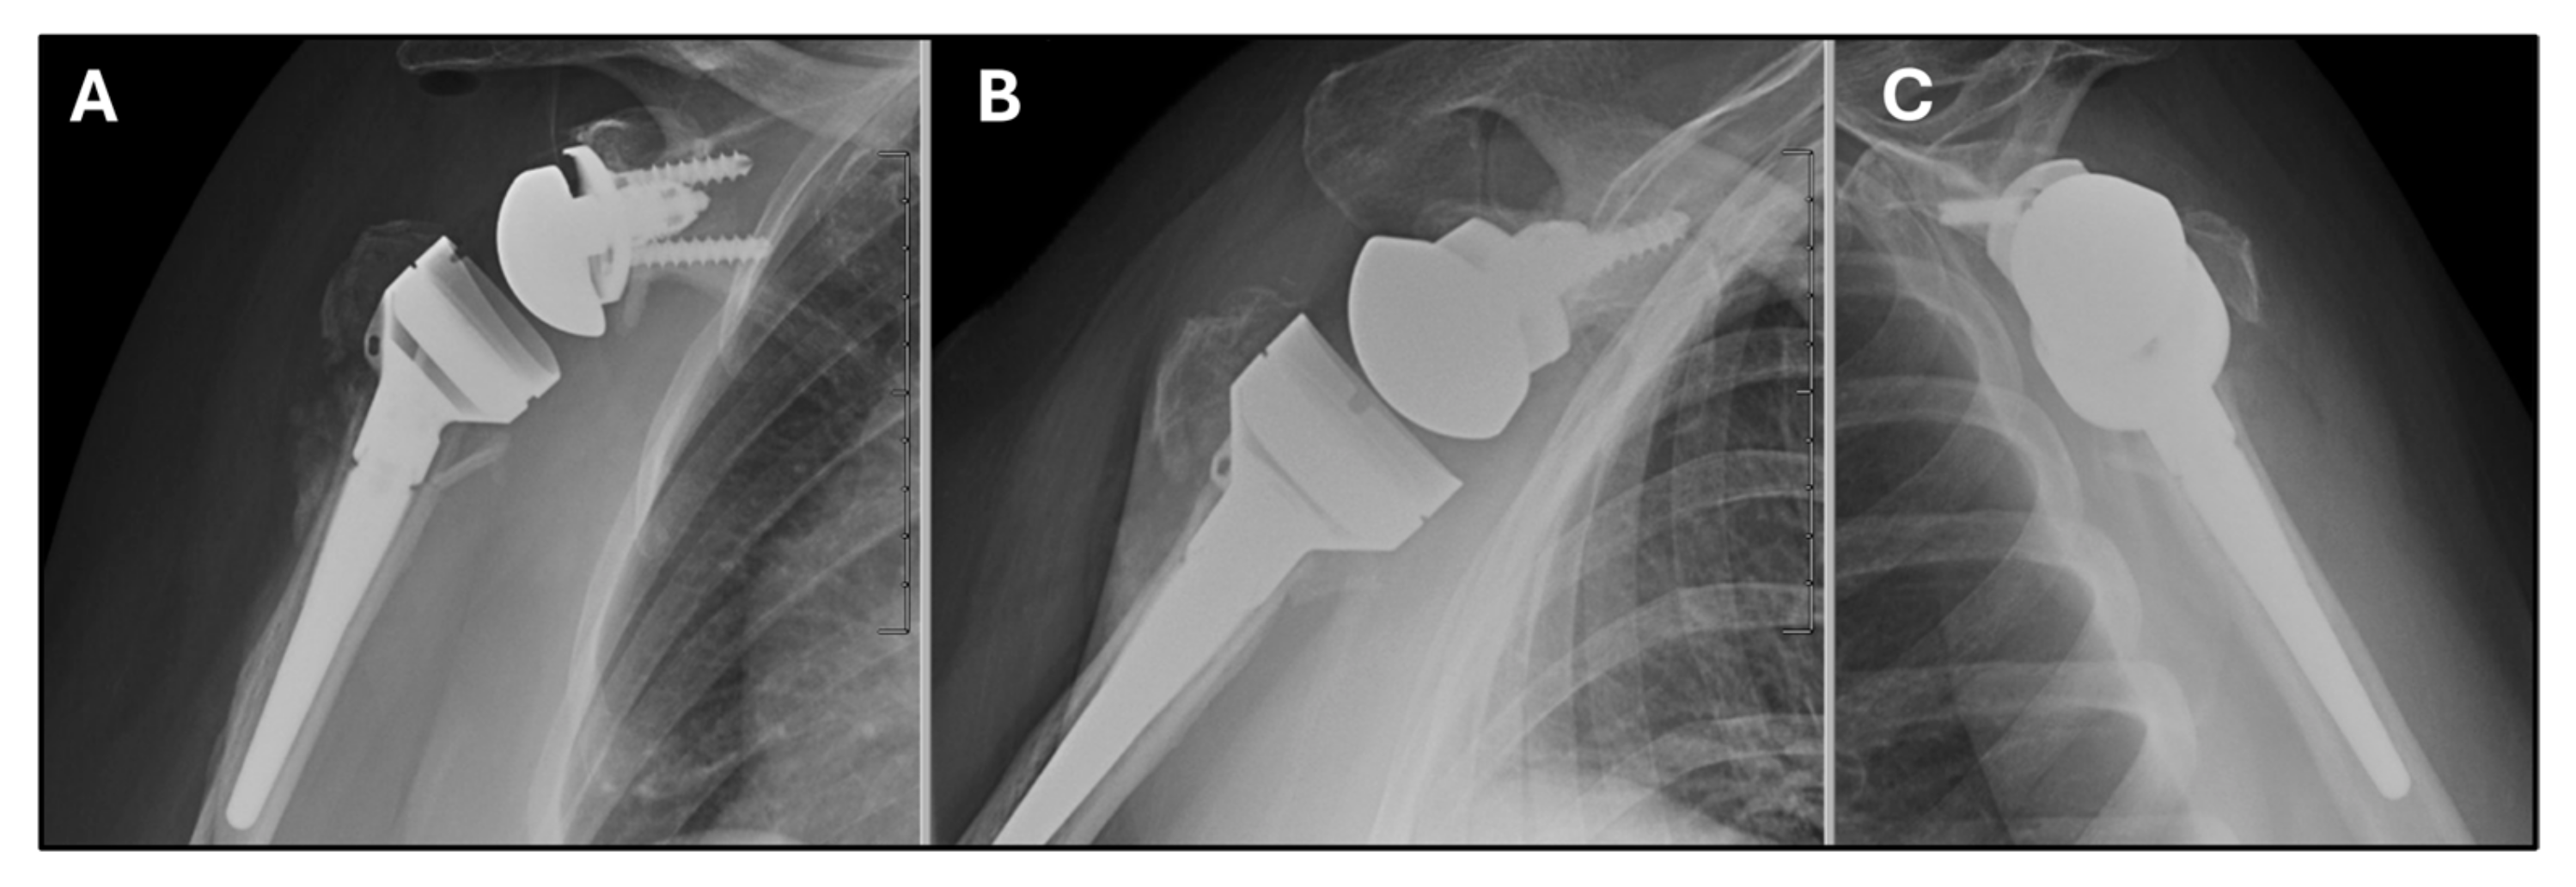

Overall, she had an uncomplicated post-operative course and reported gradual resolution of pain. She was seen back in the office at 2 weeks for suture removal. At the 6-week follow-up, her radiographs showed evidence of maintained tuberosity reduction and alignment (Figure 7), and physical therapy was started at this time. At 3 months she had improvement in her pain but continued to have some weakness with forward elevation. By her final in-office visit at 5 months postop, she was able to achieve 110 degrees of active forward elevation, unfortunately we do not have internation and external rotation values recorded in the chart for this final visit. At this visit she reported return to her pre-injury activities including independence with ADLs, ambulation with a rolling walker for assistance, and the ability to perform overhead hygiene such as curling her hair.

Figure 7. Radiographs of the right shoulder at 6 weeks post-op showing reverse total shoulder arthroplasty with maintained tuberosity reduction and alignment. (A) Grashey view. (B) Velpeau view. (C) Scapular Y view.